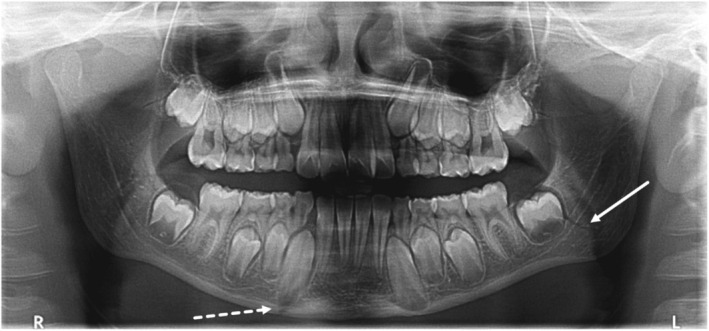

Mandible fractures are relatively uncommon despite the mandible being the most commonly fractured facial bone in the paediatric population. The aetiology of mandible fractures can be categorized as intentional (e.g. as a result of assault, peer-to-peer violence, family violence) or non-intentional (e.g. as a result of falls, motor vehicle crashes, sporting incidents). Peer-to-peer violence affects up to a third of male school aged children in Australia. This case report details the case of a paediatric patient with bilateral mandibular fractures who presented to a general dental practice after an episode of peer-to-peer violence. Clinical examination, radiographic findings and treatment are reported. This paper explores the experience and impact of peer-to-peer physical violence on the individual and his family. A review of the relevant literature is presented. © 2024 Australian Dental Association.

尽管下颌骨是儿科最常见的面部骨骼骨折,但下颌骨骨折却相对并不常见。下颌骨骨折的病因可分为故意伤害(如殴打、同伴间暴力、家庭暴力)和非故意伤害(如跌倒、车祸、体育运动事故)。在澳大利亚,多达三分之一的男性学龄儿童受到同伴间暴力的影响。本病例报告详细介绍了一名患有双侧下颌骨骨折的儿科患者的病例,该患者是在同伴暴力事件后到一家普通牙科诊所就诊的。文中报告了临床检查、放射学检查结果和治疗方法。本文探讨了同伴间身体暴力对个人及其家庭的经历和影响。并对相关文献进行了综述。© 2024 澳大利亚牙科协会。